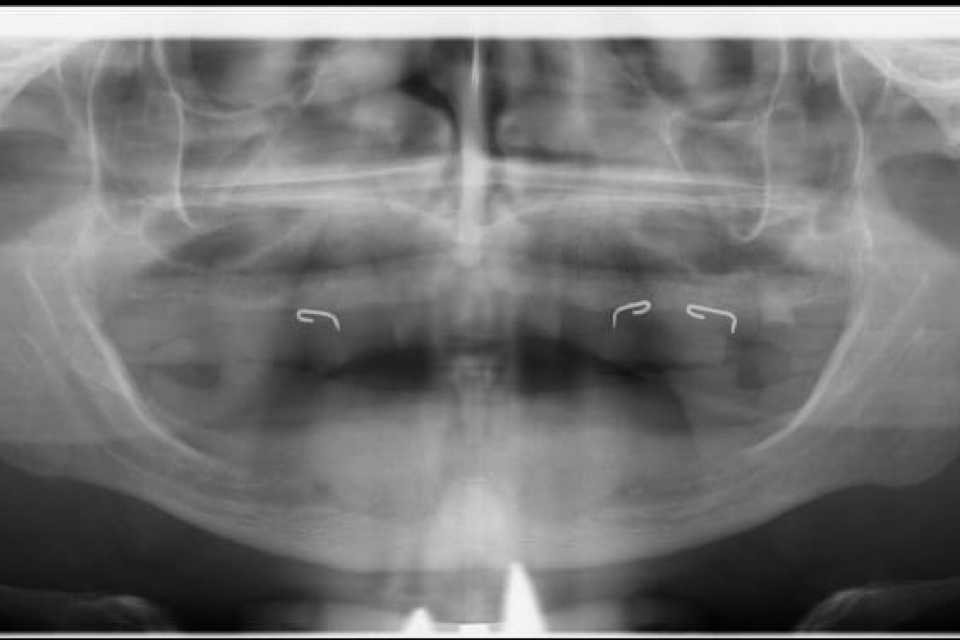

Pacient în vârstă de 41 de ani, purtător de proteze dentare mobile de aproximativ 5 ani, cu resorbții osoase severe la nivelul maxilarului și al mandibulei, s-a prezentat în cadrul clinicii noastre cu dorința reabilitării orale fixe cu ajutorul implanturilor dentare.

Cazul a fost o adevărată provocare, nu numai chirurgical, dar și protetic. Prin prisma resorbției osoase severe maxilare în zona frontală și a purtării îndelungate a protezelor mobile, la momentul consultului inițial, pacientul prezenta un etaj inferior al feței micșorat cu profil concav .